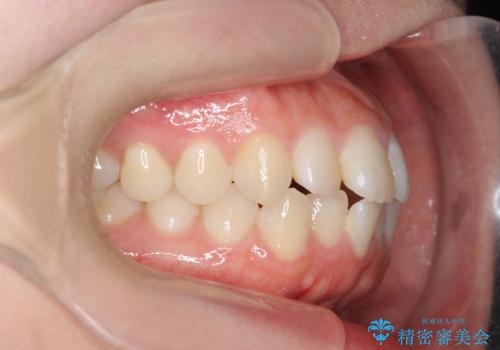

前歯のすれ違い インビザラインで行うマウスピース矯正

- 前歯のガタつき、でこぼこ、前後が逆になっている噛み合わせの改善を求めて来院されました。

治療の装置が目立たず歯ブラシのしやすいマウスピース矯正インビザラインでの治療を計画します。

20時間/日の装用時間をしっかりと守っていただき、きれいな歯並びを手に入れることができました。